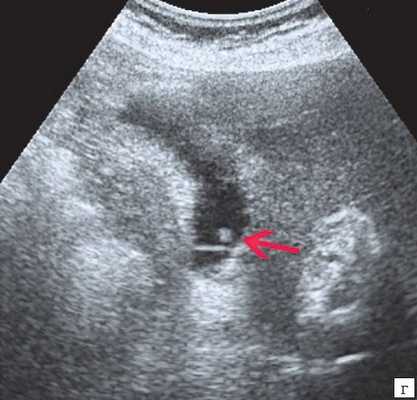

![Эхограмма - одиночный полип в желчном пузыре (2г)]()

г) Одиночный полип в желчном пузыре.

Характер ножки полипа традиционно учитывается в онкологической практике как признак, ассоциированный со злокачественной природой образования. Вероятность возможной малигнизации больше, если у него имеется широкое основание, а не тонкая ножка. Однако необходимо принимать во внимание возможность ложноположительной диагностики широкого основания при полипах больших размеров из-за их ограниченной смещаемости в просвете желчного пузыря. Дрожание, напоминающее пламя свечи, наблюдается у полипов небольших размеров и вытянутой формы, и указывает на их тонкую ножку 9.